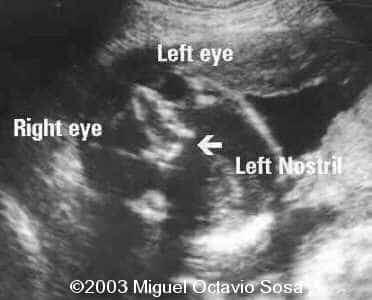

19-year-old primigravida. During third week of pregnancy, she is vaccinated with anti-measles vaccine, without knowing about the pregnancy. There are no important details before the pregnancy. These are images of the face of the fetus. Pay specific attention to the midface.

19-year-old primigravida. During third week of pregnancy, she is vaccinated with anti-measles vaccine, without knowing about the pregnancy. There are no important details before the pregnancy. At 22nd week, an ultrasound is performed demonstrating a single nasal channel on the left side and absence of right nostril.